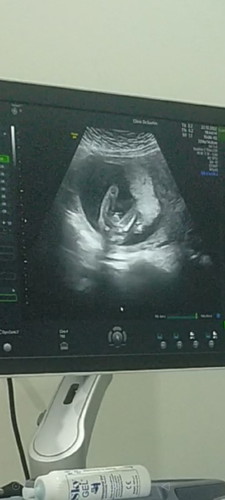

ขอสอบถามแม่ๆหน่อยค้า ใครพอจะมองออกบ้าง👶

อยากทราบว่าน้องเพศอะไรค่ะ แม่ลุ้นมากค้า ตื่นเต้น ป่ะป๊าน้องรู้แล้วเพราะแอบยิบตากับลุงหมอ🤣🤣 ปล.#หมอกับป่ะป๊าไม่บอกแม่ แม่ภาวนาให้เป็นเพศชายค้า เพราะที่บ้านมี2สาว ตุ๊กตาหน้ารถแล้วค่า 2สาวที่บ้านก้อยากได้น้องชายบ้าง🥰 #ใครพอมองรูปแล้วทราบบ้างค้า🤣 #ทีมมิถุนา65 #คุณแม่ลูก3